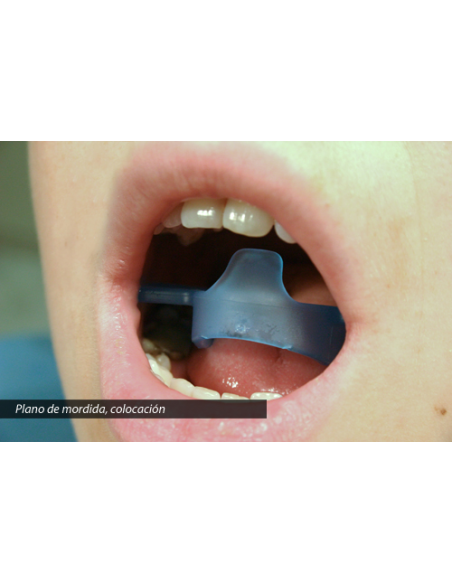

L’Otturatore Buccale Semipermeabile è un dispositivo progettato per rieducare la respirazione orale e favorire il corretto passaggio dell’aria attraverso il naso.

Agisce come una barriera parziale che limita gradualmente il flusso d’aria orale, riducendo progressivamente l’abitudine a respirare con la bocca, una delle cause più comuni di malocclusioni dentarie, recidive ortodontiche e disfunzioni oro-facciali.

La sua struttura presenta piccoli fori che permettono un passaggio d’aria controllato, evitando la sensazione di soffocamento e consentendo un adattamento naturale. Le creste periferiche stimolano inoltre la muscolatura labiale, migliorando la competenza delle labbra e il tono periorale.

L’Otturatore Buccale Permeabile rappresenta la prima fase del percorso di rieducazione della respirazione orale.

Grazie ai fori ampi, consente un passaggio d’aria moderato, permettendo al paziente di adattarsi progressivamente a respirare dal naso senza fastidio.

Questo dispositivo aiuta a normalizzare la funzione respiratoria e a ridurre l’abitudine alla respirazione orale, migliorando nel tempo la postura linguale e labiale.

Le creste periferiche favoriscono il lavoro dei muscoli delle labbra, migliorando la chiusura orale e la competenza labiale.